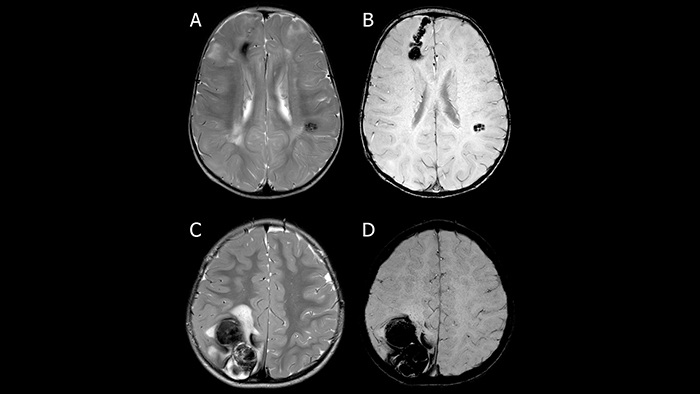

SWIp активно используется для визуализации точечных кровоизлияний в глубоком подкорковом белом веществе, которые сопровождают диффузные аксональные повреждения головного мозга. Клинический прогноз зависит от числа кровоизлияний, а недавнее исследование [11] выявило связь между кровоизлияниями в ряде глубоких подкорковых областей головного мозга и повышенной вероятностью нарушения исполнительных функций у подростков. Таким образом, остро стоит необходимость обнаружения и точной локализации церебральных микрокровоизлияний [12]. Эти точечные патологические изменения при диффузно-аксональном повреждении не столь заметны при использовании традиционных методик МРТ-визуализации (рис.8). Использование фазовой информации обуславливает более высокий контраст кровоизлияний на SWI изображениях, как следствие, даже чувствительные к неоднородностям поля T2* последовательности уступают SWI изображениям по чувствительности при диагностике диффузных аксональных повреждений [13].

Sparacia et al. показали [18], что изображения, полученные благодаря методике SWIp на МР-томографе Achieva 1.5 Тл, демонстрируют более чем в 2.5 раза больше кавернозных ангиом, чем T2*-взвешенные изображения. При этом авторы отмечают больший размер и более высокую четкость очагов поражения на SWI изображениях, что позволяет выявлять незаметные на T2* изображениях очаги и способствует более точной постановке диагноза.